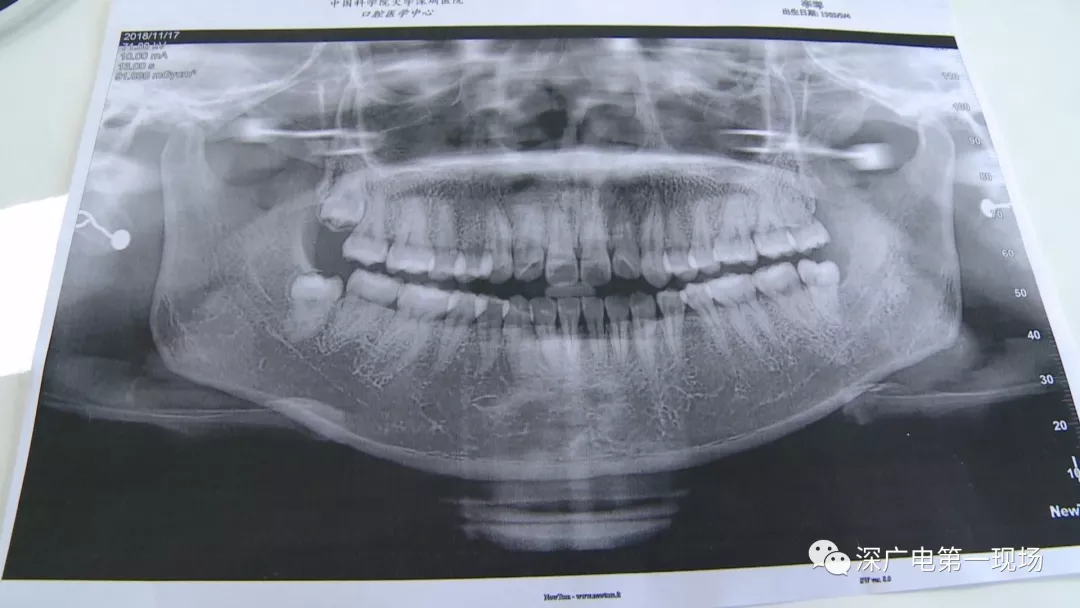

拔一顆智齒一千六?! 深圳這位女士默默的放下了賬單……

隨后,李女士在網(wǎng)上查詢,發(fā)現(xiàn)拔智齒的收費(fèi)都是參差不齊,也沒有參考標(biāo)準(zhǔn)。在李女士提供的拔牙收費(fèi)單上,記者注意到,除了一些拔牙必用的藥物外,還有一些輔助工具的費(fèi)用。

中國科學(xué)院大學(xué)深圳醫(yī)院口腔科主任賈岳介紹,對于不同患者的牙齒,它的治療方法都不一樣,所以不同牙齒,醫(yī)院收費(fèi)的標(biāo)準(zhǔn)也各不相同。牙齒的治療方案,都是根據(jù)患者牙齒具體情況來制定,然后再去收費(fèi),同時也會參考病人實際情況來做不同的治療項目。